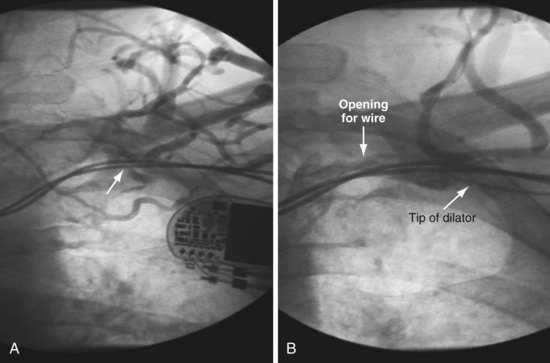

It is important to remember that “subclavian” is commonly used shorthand for the axillary/subclavian/innominate vein. Some degree of subclavian vein occlusion is common in patients with existing leads. The severity of the obstruction is often defined based on a venogram performed by contrast injection through an arm vein (peripheral venogram). When the peripheral venogram reveals an occlusion, it is best to enter the vein as far peripheral to the occlusion as possible to provide a stable access for approaching the occlusion (Fig. 23-8). A standard short J wire is then advanced to the occlusion and the needle exchanged for the dilator from a 5F sheath. The dilator is then connected to the Y adapter of the injection system (Fig. 23-9), and contrast is injected at the site of occlusion.

The length and severity of the occlusion may be either overestimated or underestimated by the peripheral venogram. In Figure 23-10 the peripheral venogram reveals extensive collaterals, and the occlusion appears complete in A, whereas in B, contrast injected at the site of occlusion demonstrates an opening that was easily crossed with an angled glide wire and torque device. In Figure 23-11, despite collaterals, the peripheral venogram in A suggests an opening that will be easy to cross, whereas in B, with injection of contrast at the occlusion, there is a total occlusion over 2 cm. Although it is important to perform contrast injection at the site of obstruction, the true, clinically relevant severity of obstruction is ultimately determined by whether a wire will cross the obstruction. For example, the venogram may demonstrate a hopelessly long, total occlusion, but the wire may cross easily (Fig. 23-12). Conversely, the stenosis may be short but impossible to cross with a wire. Accordingly, we define the obstruction based on how difficult it is to deliver a wire across the occlusion, as follows: